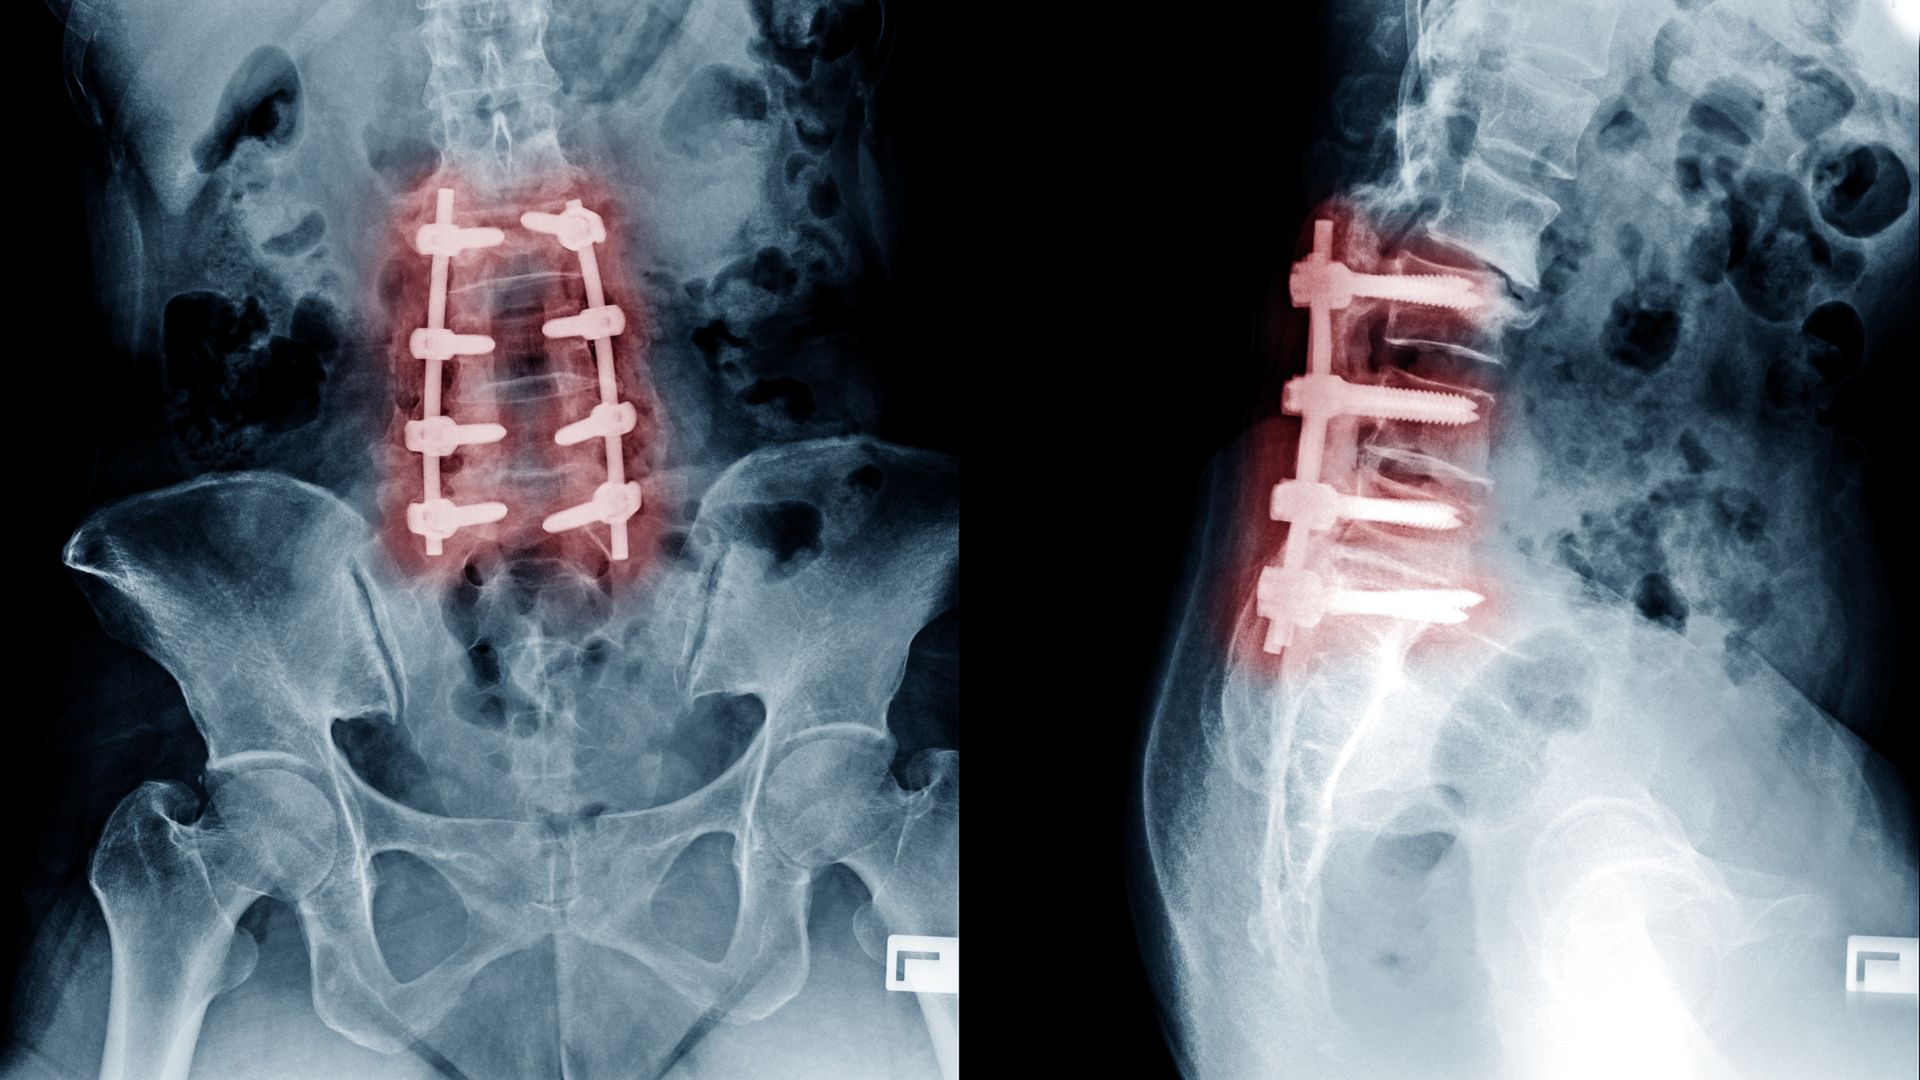

4. Spinal Stenosis:

Spinal stenosis is characterized by the narrowing of the spinal canal, which puts pressure on the nerves and spinal cord. This pressure on the nerves can result in back pain and symptoms such as leg pain, numbness, and weakness. Spinal stenosis is often age-related but can also be caused by other factors such as arthritis or injuries. Treatment options may include physical therapy, medication, and in severe cases, surgery.